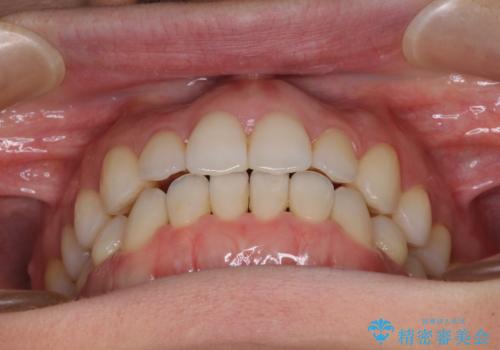

前歯の叢生とオープンバイト インビザラインでの矯正治療

- 前歯の開咬を気にして来院された患者様です。

開咬の治療は、前歯を閉じるように動かすとともに、上下臼歯を圧下(骨内にめり込ませる)させることで進めて行きます。

インビザラインは臼歯の圧下を効果的に行えるため、インビザラインを用いて矯正治療を行うこととしました。